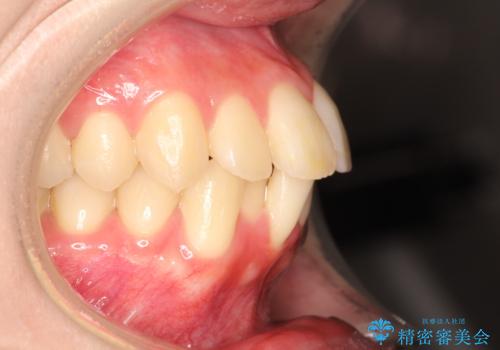

- 前歯が出ているため口が閉じにくく、横顔が気になるとのことで来院された患者様です。。

上下の前歯が前方に傾斜しており、口唇の突出感がありました。

上下左右の前から4番目の歯を抜歯して、上下の前歯を後方に移動させる計画としました。